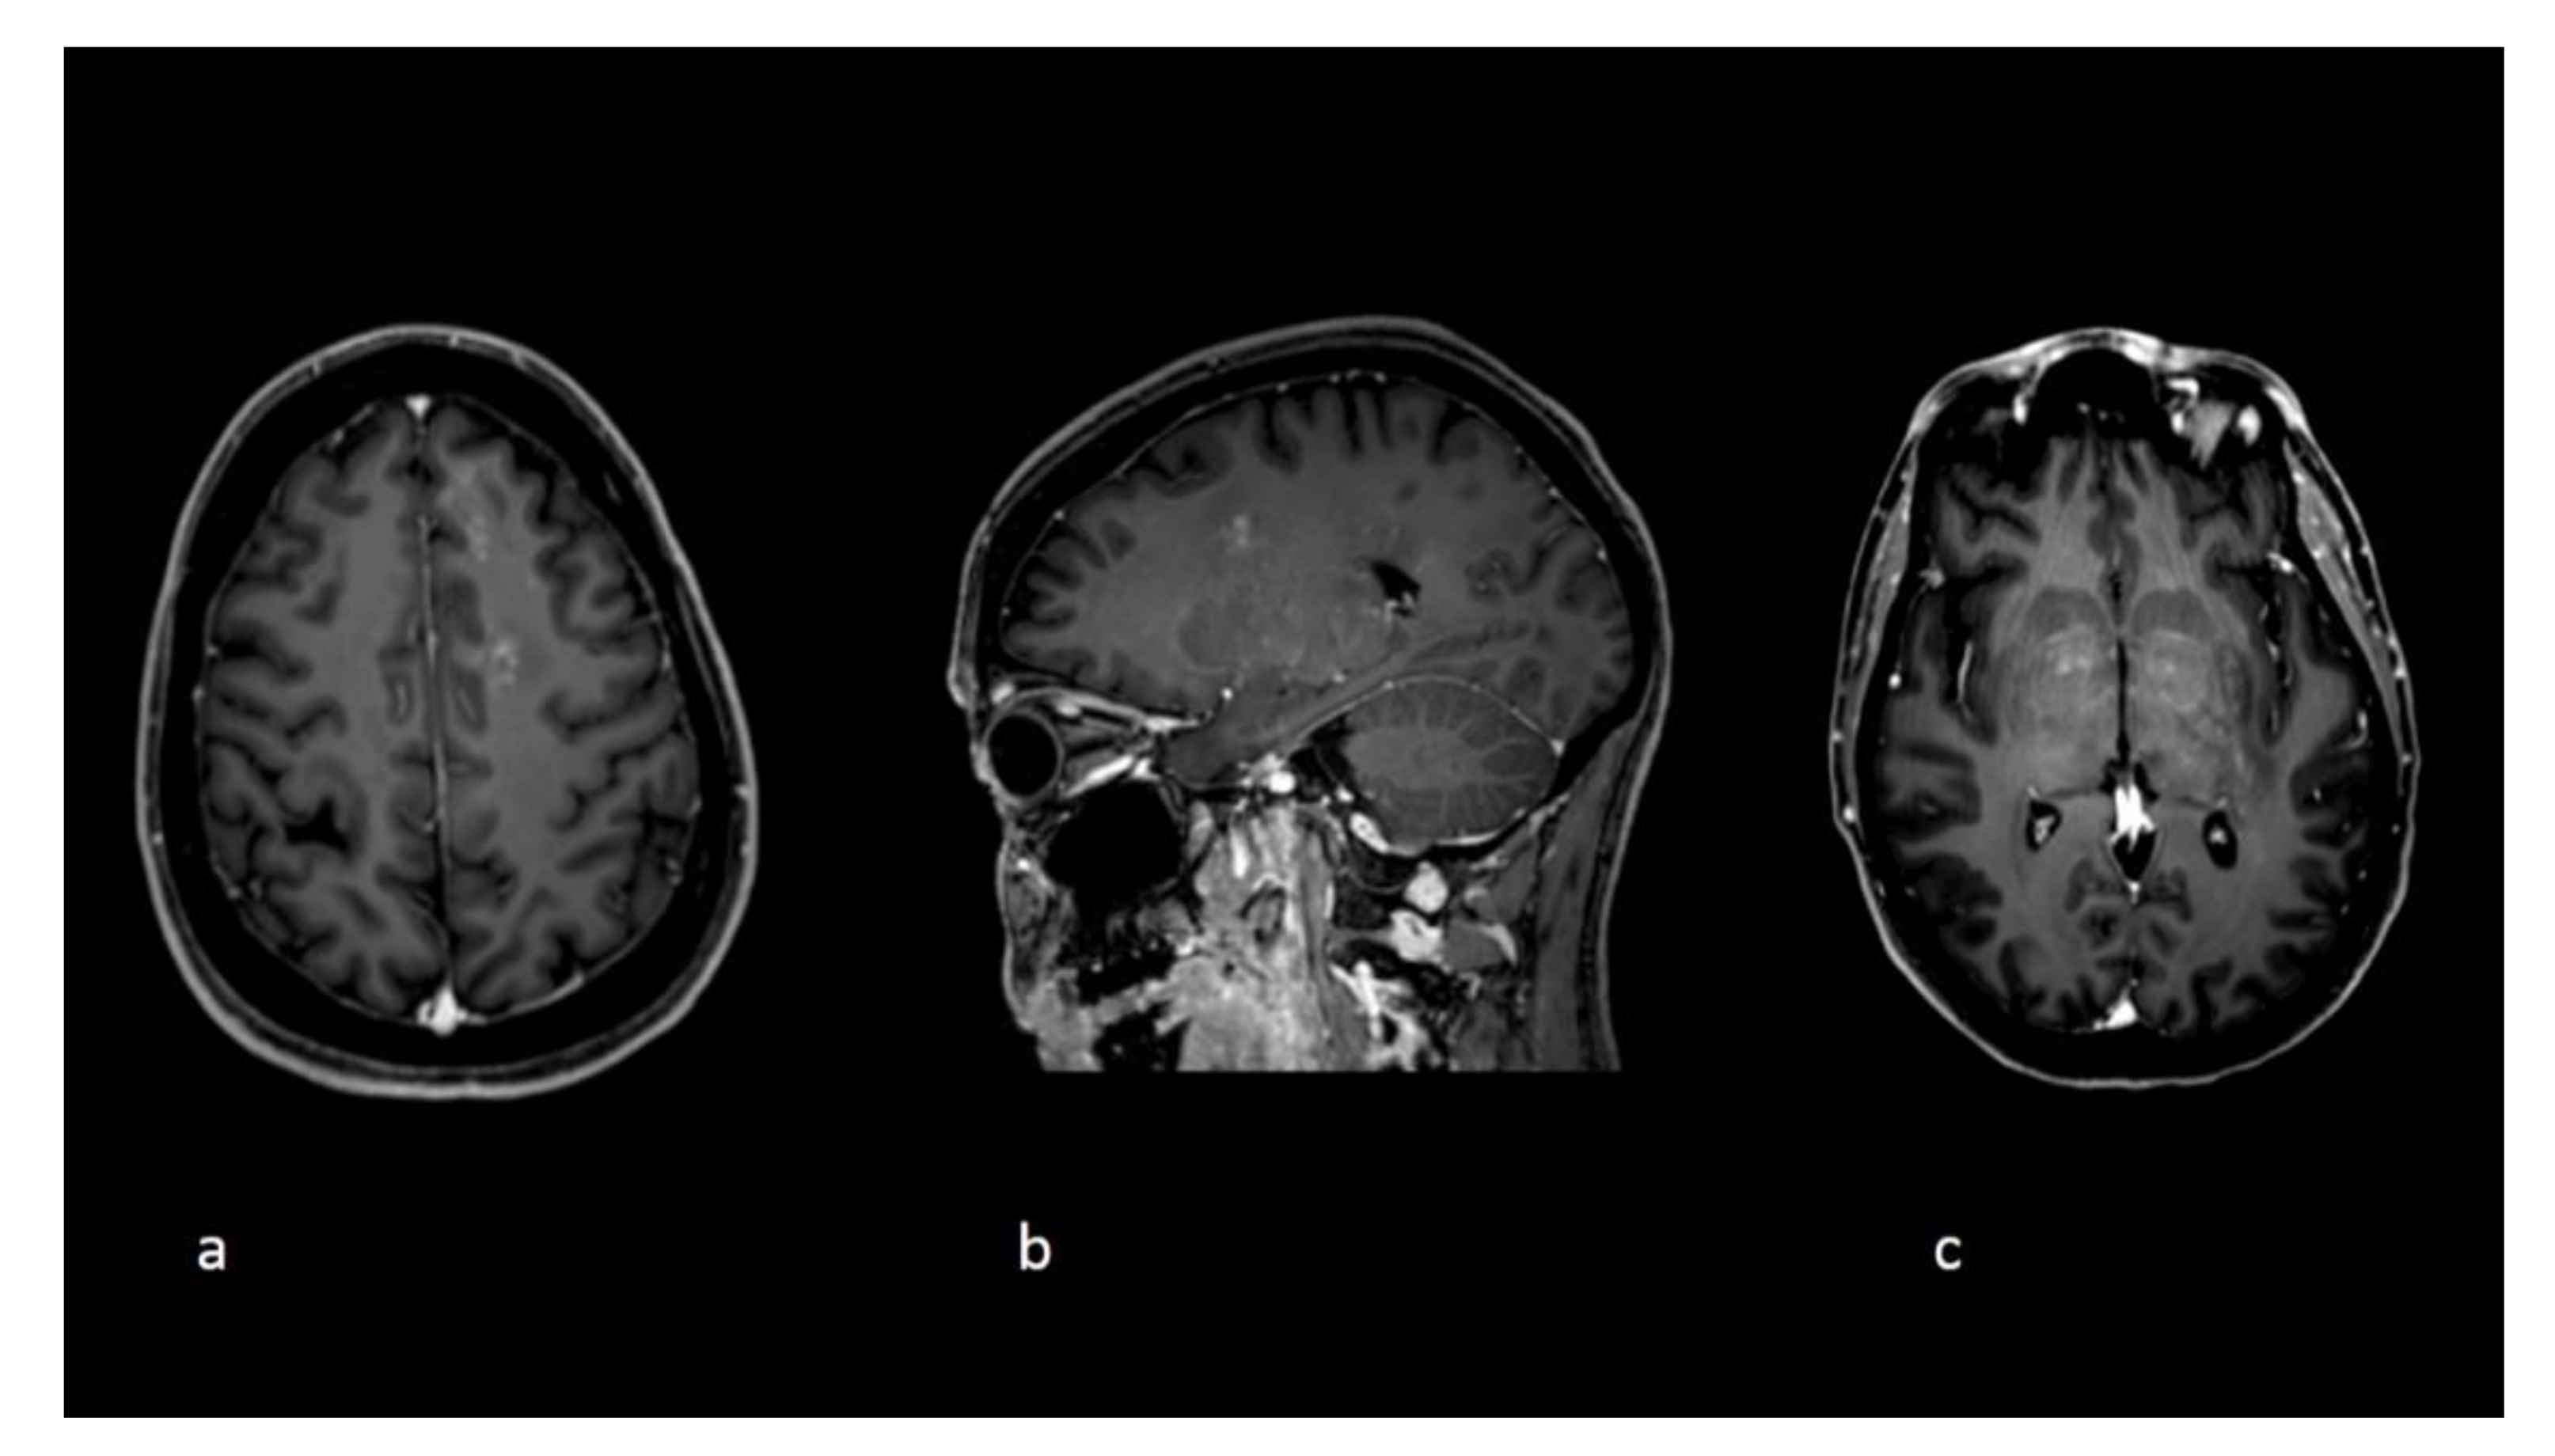

Figure 2.

Follow-up imaging at the time clinical deterioration. Axial (a,c) and sagittal (b) T1 postgadolinium images demonstrate new white matter lesions with a punctuate pattern of enhancements and an overall radiological pattern different compared to the initial exams.